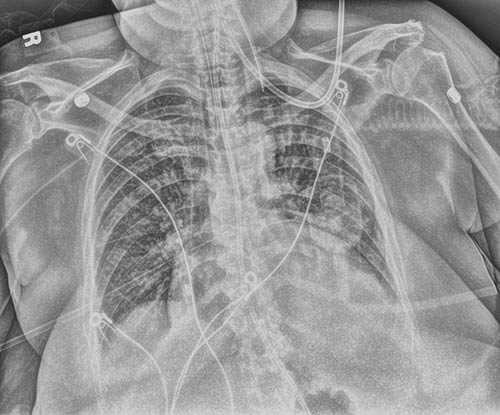

Tube and Line

Be sure with a single exposure. Tube & Line Enhancement creates a companion image and uses optimized processing for clearer, easier visualization of PICC lines and tubes. It increases confidence that tubes and lines are placed correctly – and remain in position.

Modified

Original